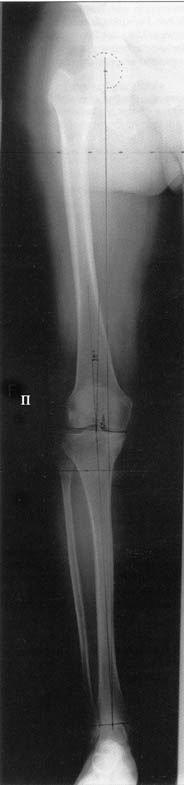

AC> Обратилась дама 25 лет. Вынуждена ходить в брюках из-за genu varum,

AC> что побудило обратиться за коррекцией.

. On the right leg you can see some of the tools (from the tool bar above) applied to demonstrate a mild mech-axis varus of about 5 degrees.

In essence she has a mild mech-axis varus of 7 degrees with some contribution from the femur (2) degrees and more from the tibia (6 degrees), none from the joint.